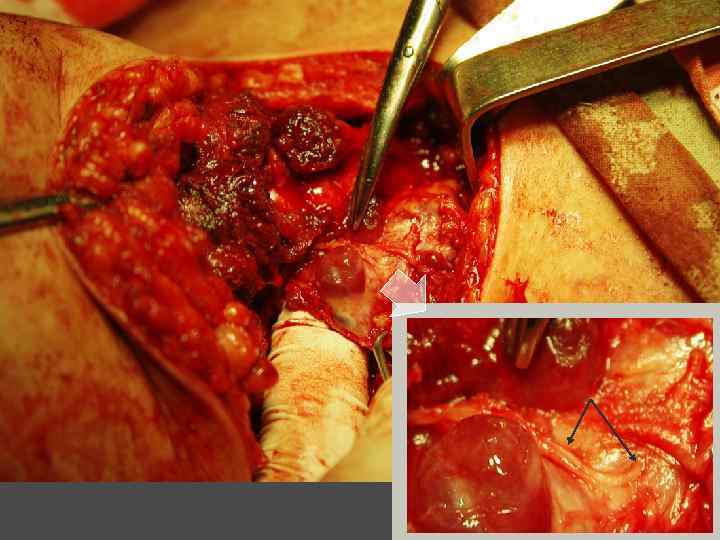

ГИПЕРПАРАТИРЕОЗ

Гиперпаратиреоз - синдром, связанный с усиленной выработкой паратиреоидного гормона гиперплазированными или опухолево-измененными околощитовидными железами.

ПАРАЩИТОВИДНЫЕ ЖЕЛЕЗЫ

ЛЕЧЕНИЕ Консервативное – возможно только у больных вторичным гиперпаратиреозом, при уровне паратгормона не превышающим 800 пг/мл. Хирургическое – паратиреодэктомия.

ЭКТОПИРОВАННАЯ В ТИМУС ПАРАЩИТОВИДНАЯ ЖЕЛЕЗА